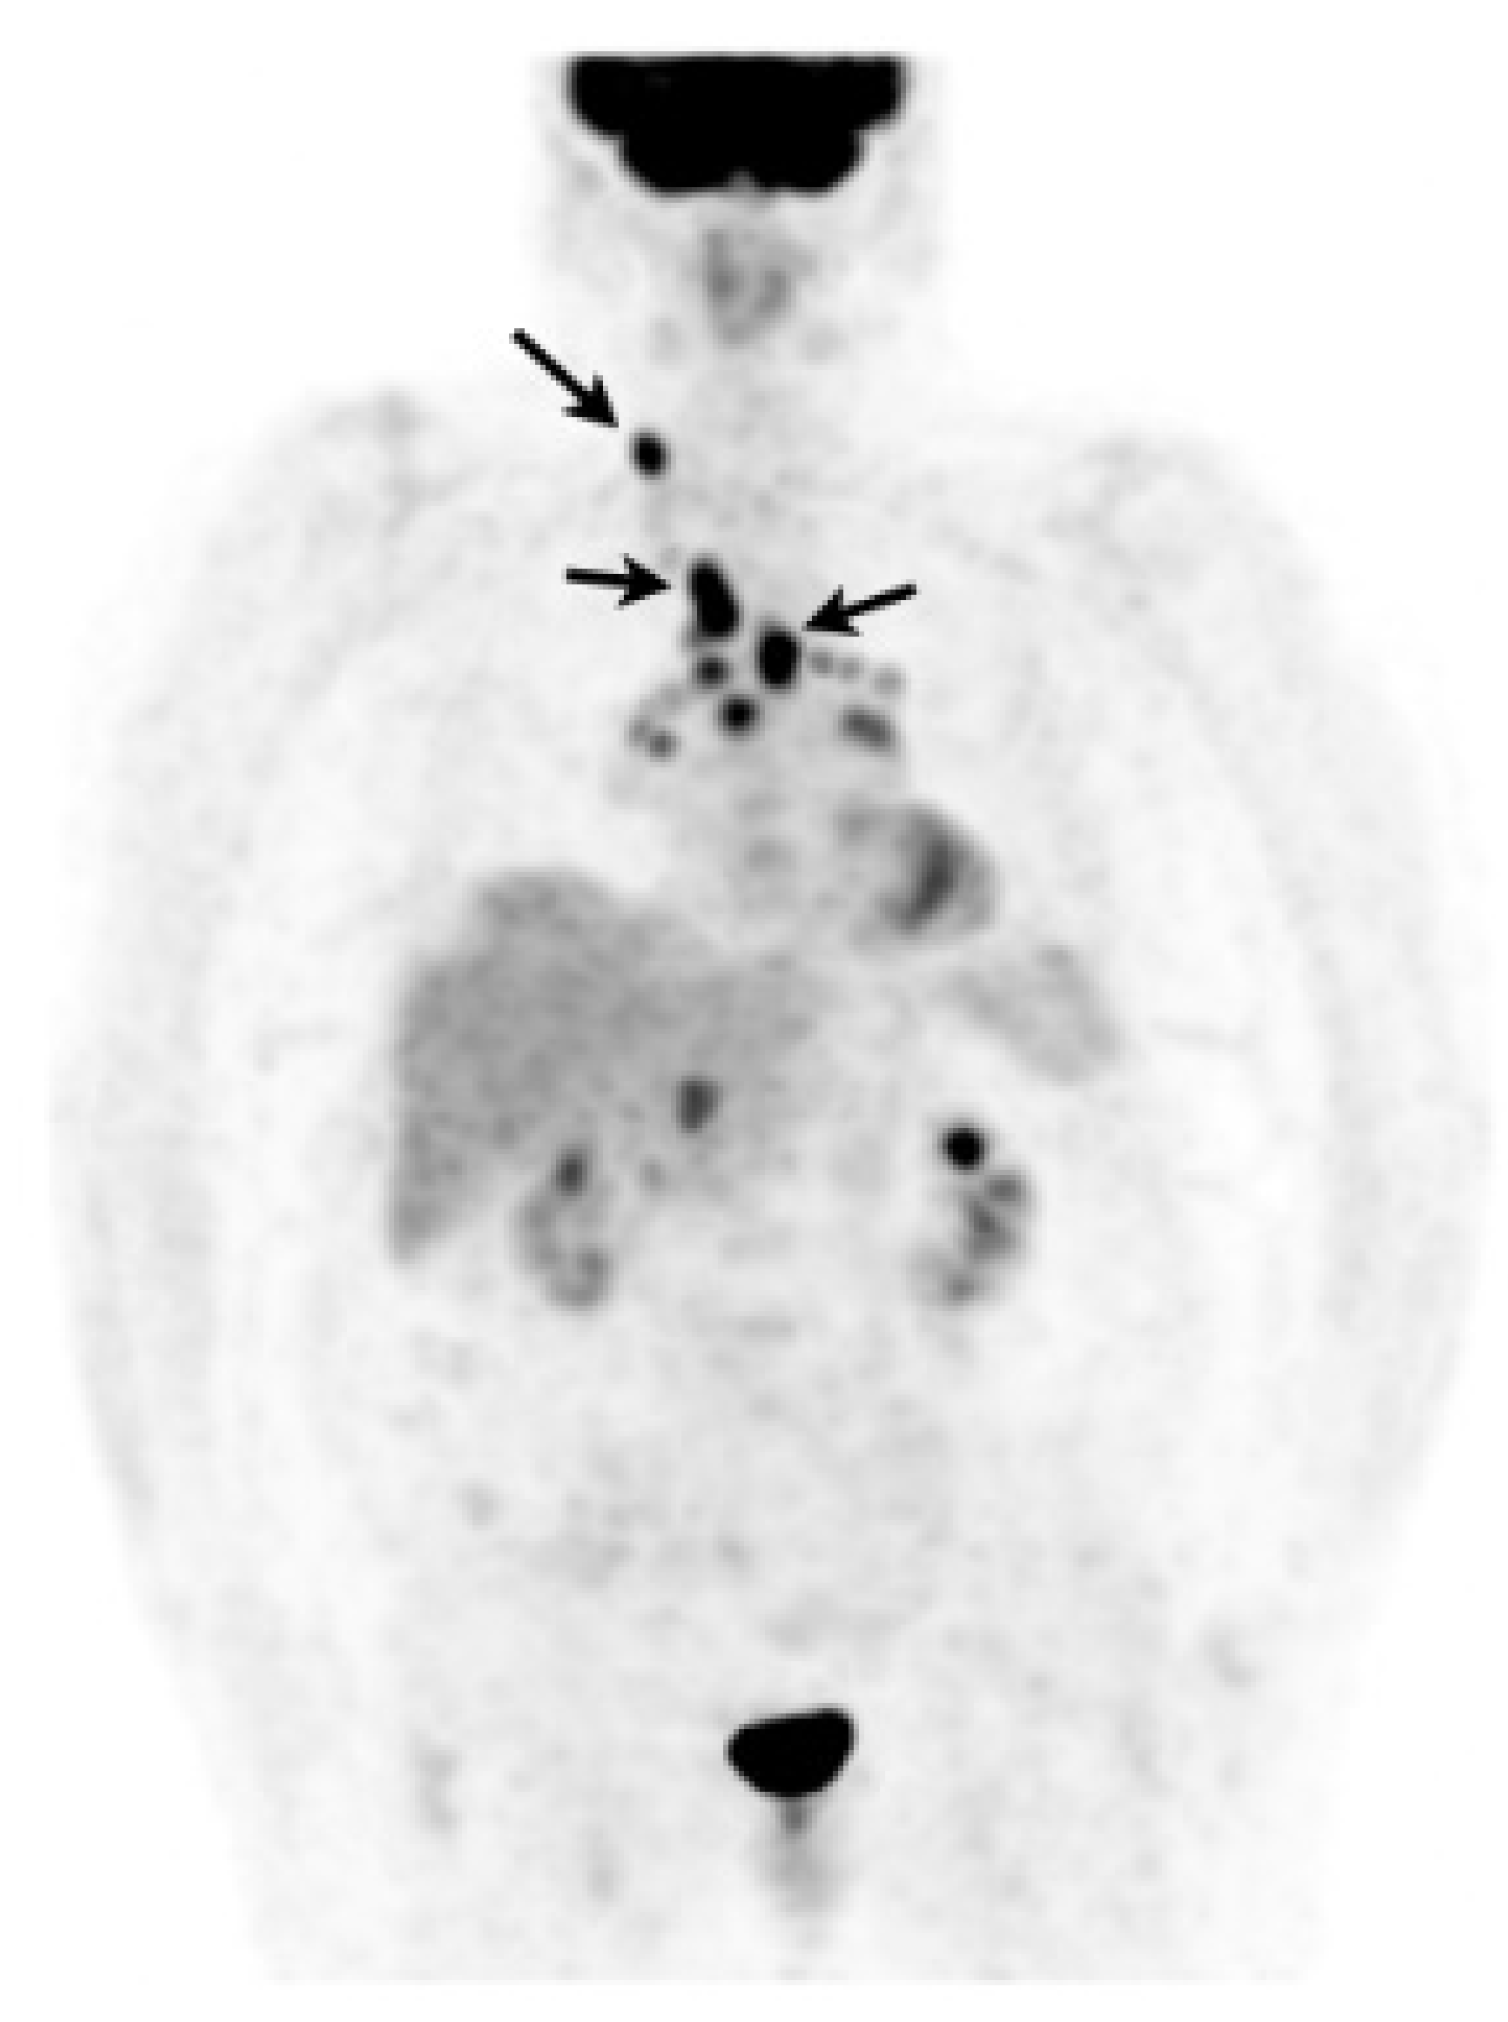

In case of poorly accessible organ localization without superficial nor thoracic manifestation (e.g., cardiac or neurosarcoidosis) 18F-FDG PET may show a suggestive sarcoid-like uptake pattern with hypermetabolic mediastinal and hilar lymph nodes, whether or not combined with lung parenchymal active disease which supports the likelihood of sarcoidosis and orientates a mediastinoscopy [205]. 18F-FDG PET may sometimes reveal smoldering superficial localizations, for example, cervical lymph nodes which are easily accessible to biopsy (Figure 9) [206]. The value of EBUS-guided lymph node sampling in patients with hypermetabolic lymph nodes on 18F-FDG PET remains to be studied.

Figure 9.

Caucasian woman (78 years old) suffering from bilateral unexplained panuveitis. Whole body 18F-FDG PET (maximum intensity projection anterior view) demonstrated significant bilateral hilar, mediastinal and right supraclavicular lymph nodes uptakes (black arrows) while there was no node enlargement on chest CT. A subsequent supraclavicular node dissection revealed noncaseating epithelioid granulomas consistent with sarcoidosis. Special staining and culture for mycobacteria were negative.